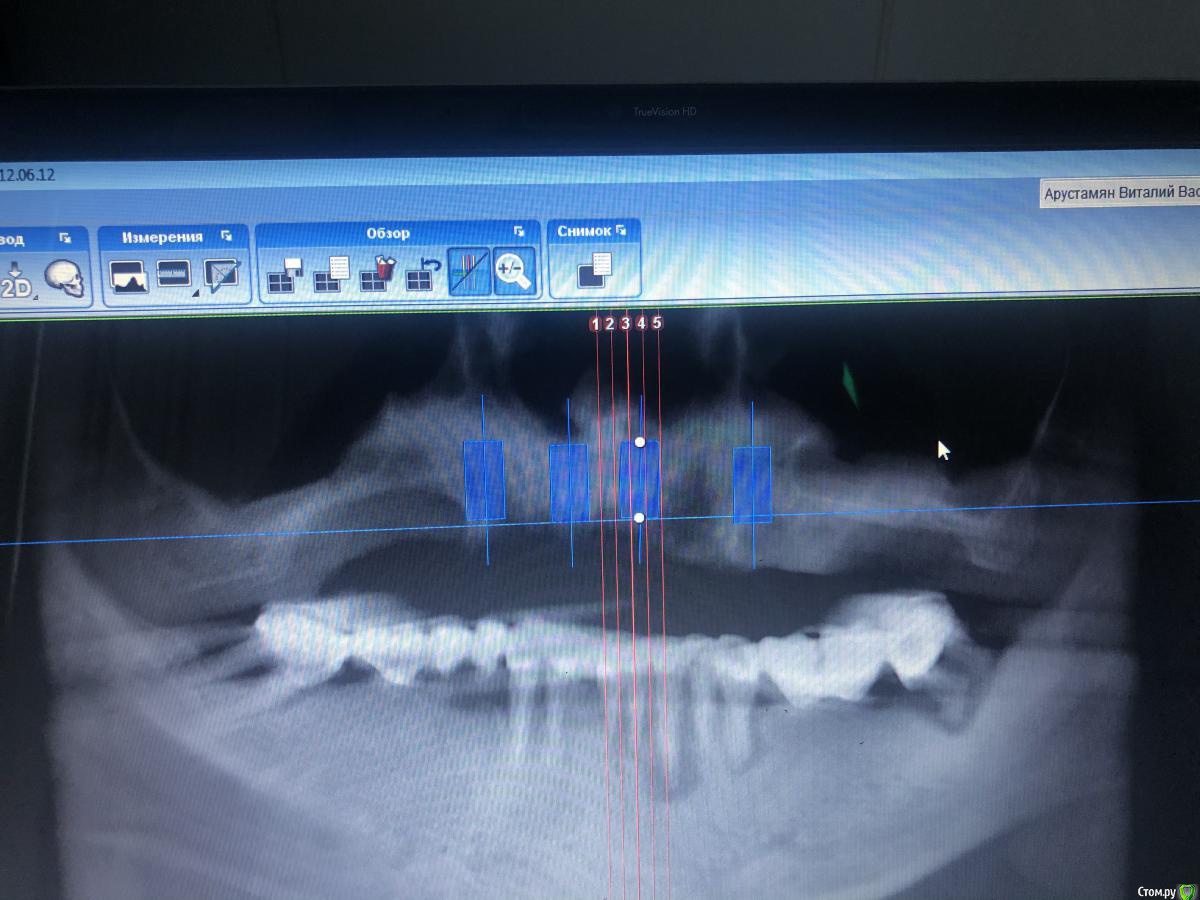

Александр07 Опубликовано 1 июля, 2020 Поделиться Опубликовано 1 июля, 2020 Коллеги доброго дня, пац 55-60 лет, хочет чтобы было красиво и крепко держалось, такая ситуация во рту, планируем операцию на вчКак видите примерно в обл 1.4-1.6 дефект по высоте, размышляю по поводу установки 1.1,1.3, 2.2,2.4 с расщеплением в обл 1.3, под протез на балке, Врем конструкция на импл , даже при условии что получится без большой подсадки, не рискнул бы- крупный мужчина, будет давать нагрузку, если ставить Мини импл то планировал бы позиции 2.1,2.5, 1 сегмент пока не ясно куда ставить ) По аугментации в обл 1.5-1.6, что посоветуете- делать /не делать, одновременно с фронтом или отдельно, или ограничиться тем планом по балке что написал выше , В обл 2.5-2.6 синус нужен trim.F286E467-8CC6-421B-ACE6-47434003E04E.MOV Ссылка на комментарий

Александр07 Опубликовано 14 августа, 2020 Автор Поделиться Опубликовано 14 августа, 2020 Коллеги планируется имплантация на вч-удаление 2.4,2.6, 2.7 под ? ( ферула нет после снятие мк, можно попробовать удлинить но ортопед не особо настроен ) , здесь сложность в том что пац не может ходить без зубов, чтобы окружающие не знали об этом, Первый вариант это удаление 2.4-2.6 и капа , второй вариант это убрать 2.4,26.2,7 и импл с нагрузкой 2.4,2.5, 2.7 Вот срезы, скажите что думаете , насколько вероятно нагрузить и стоит ли, в обл 2.5 по хорошему откр с лифт, можно попробовать закрытый, 2.7 придётся смещать к перегородке межзубной Ссылка на комментарий